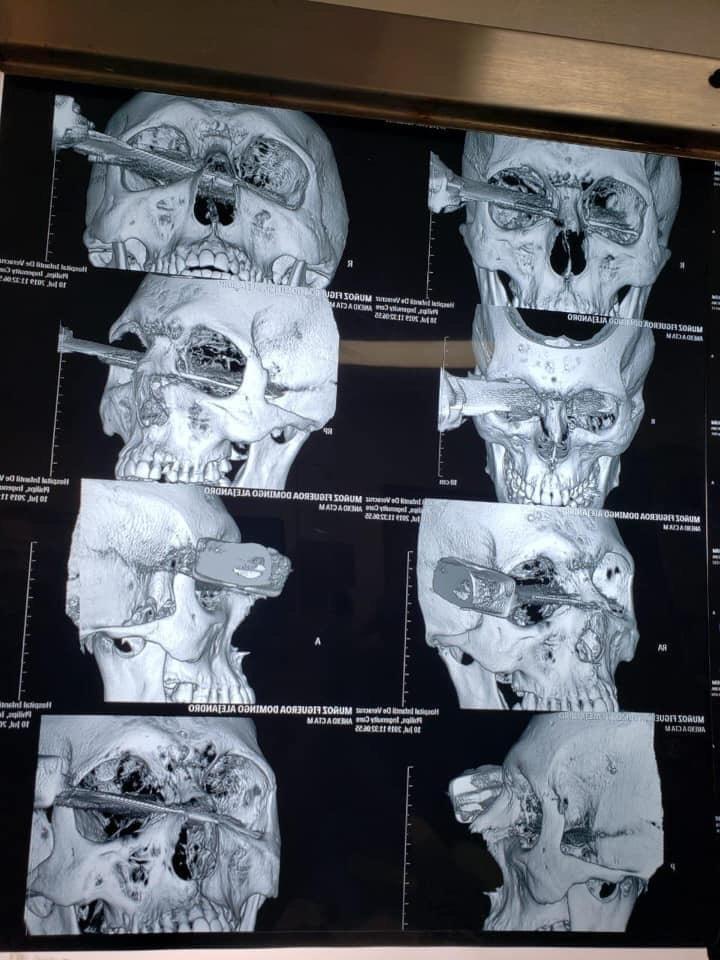

Un hombre perdió el ojo izquierdo tras ser acuchillado en medio de un pleito por un cajón de estacionamiento, en el estado de Veracruz.

En medio del pleito, uno de ellos sacó un cuchillo y se lo clavó al otro en el ojo. A pesar de ello, el agredido siguió reclamando que se trataba de una pelea “a puro puño, como hombres”

El hombre tuvo que ser sometido a cirugía para poder retirarle el cuchillo que le clavaron en el ojo y que causó severas lesiones.

En la cirugía tuvieron que participar varios integrantes del personal médico, de acuerdo a información proporcionada por el propio hospital.

Finalmente, los médicos que atendieron el caso, lograron retirar el cuchillo de la cara del hombre.